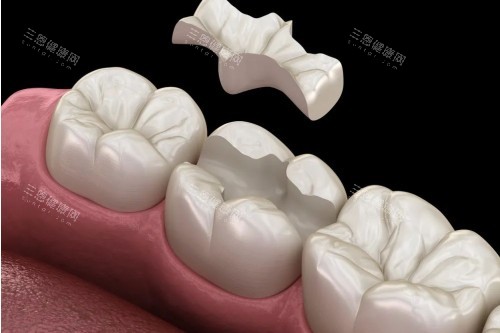

即刻负重技术:种牙当日就可以戴临时牙冠,唔使等几个月先有牙用。